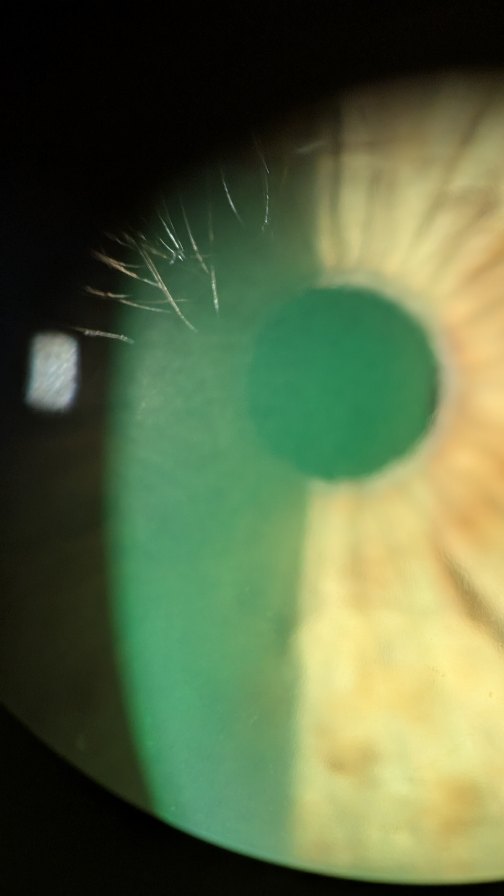

OPTOMETRY

Optometrists are trained and certified to provide a range of eye care services. As your primary eye care provider, Dr Vo aims to provide the most up to date care for her patients.